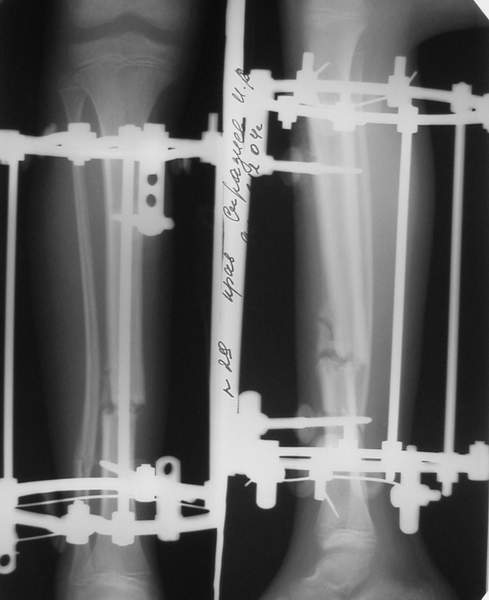

Под рукой прилагаемый пример. Как видите, "стриптиз-аппарат" (шутка проф. З.К.Башурова): 3 кольца-2 кольца-2 полукольца. В случае, который представил Евгений, характер повреждения позволил бы сразу использовать аппарат на основе 2 колец; в крайнем случае прокс. опора м.б. демонтирована сразу после репозиции.

В аттачтах №№ 1 и 2 - примеры, когда 2 кольца не позволили послеоперационно

исправить смещение фрагментов большеберцовой (по ширине и вальгусное).

А казалось бы (#2) - поиграй на штангах и все влетит.

Оперировал не я